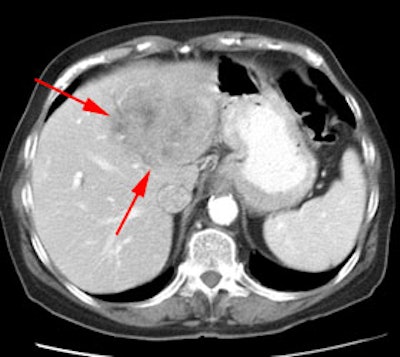

Initial staging for colorectal carcinoma: The patient below presented for evaluation of colorectal carcinoma. The CT scan demonstrated a large liver mass (red arrows) compatible with metastatic disease. The patient's cecal mass (black arrow on PET scan) was not detected on the CT study (white arrow). No other lesions were identified on the PET scan. |

|